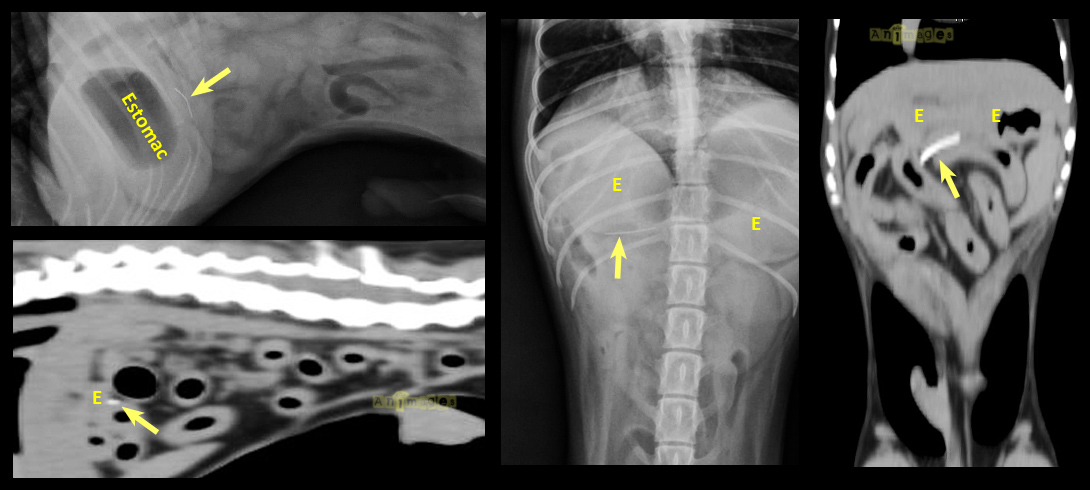

Comme la majorité d’entres vous le recommandiez, nous avons échographié l’abdomen de ce chien sans toutefois arriver à identifier le corps étranger (flèche jaune). Il faut toutefois préciser que l’estomac était légèrement dilaté par de l’air, tout comme le côlon transverse qui le longe tout juste caudalement. Il n’y avait pas de signe de perforation (air libre ou épanchement liquidien). Cependant, les gras étaient hyperéchogènes tout près du caecum qui se trouvait sous l’arche costale du côté droit. En raison de la minceur du corps étranger et pour éviter une longue chirurgie exploratrice possiblement non fructueuse, une tomodensitométrie (CT-scan) a été proposée pour en déterminer la localisation. Sur les images reformatées en différents plans (voir ci-bas), le corps étranger a été localisé dans les gras tout juste derrière le corps de l’estomac. Fait intéressant, il n’y avait pas d’air libre dans la cavité péritonéale. Ces informations ont permis au chirurgien de rapidement identifier le petit fil de métal en palpant doucement les gras derrière l’estomac. Le petit corps étranger n’était pas visible à l’oeil nu et aurait probablement été difficile à trouver sans l’aide du CT. On spécule que le petit fil de métal provenait d’une brosse à BBQ. Comme quoi il faut savoir brosser avec modération !